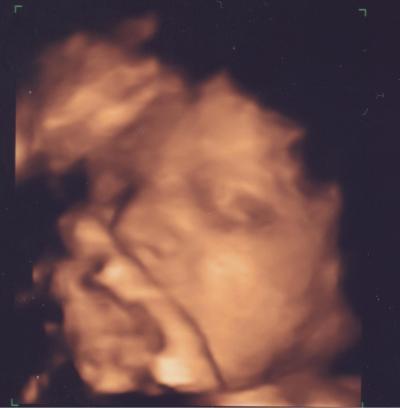

also ich war heute 2,5 h im KH zur Geburtsplanung. war recht interessant. ne wassergeburt kommt bei mir aber wegen meiner diabetes nicht in frage. alles so weit unauffällig. die oberärztin hat auch noch mal ganz genau und sehr lange das herz angeschaut. der kleene lag im schneidersitz, so dass wir leider nicht die oberschenkel messen durften. ansonsten sind die werte alle noch im normalbereich...aber eher unterer normbereich. und wegen meiner diabetes sollte der ET 26.8. auch nicht überschritten werden. find ich gut :) der kleine wiegt jetzt 1680 gramm bild im anhang...hat natürlich mal wieder die hand vorm mund

Bild zu Gespräch Geburtsplanung - Forum für August - Mamis